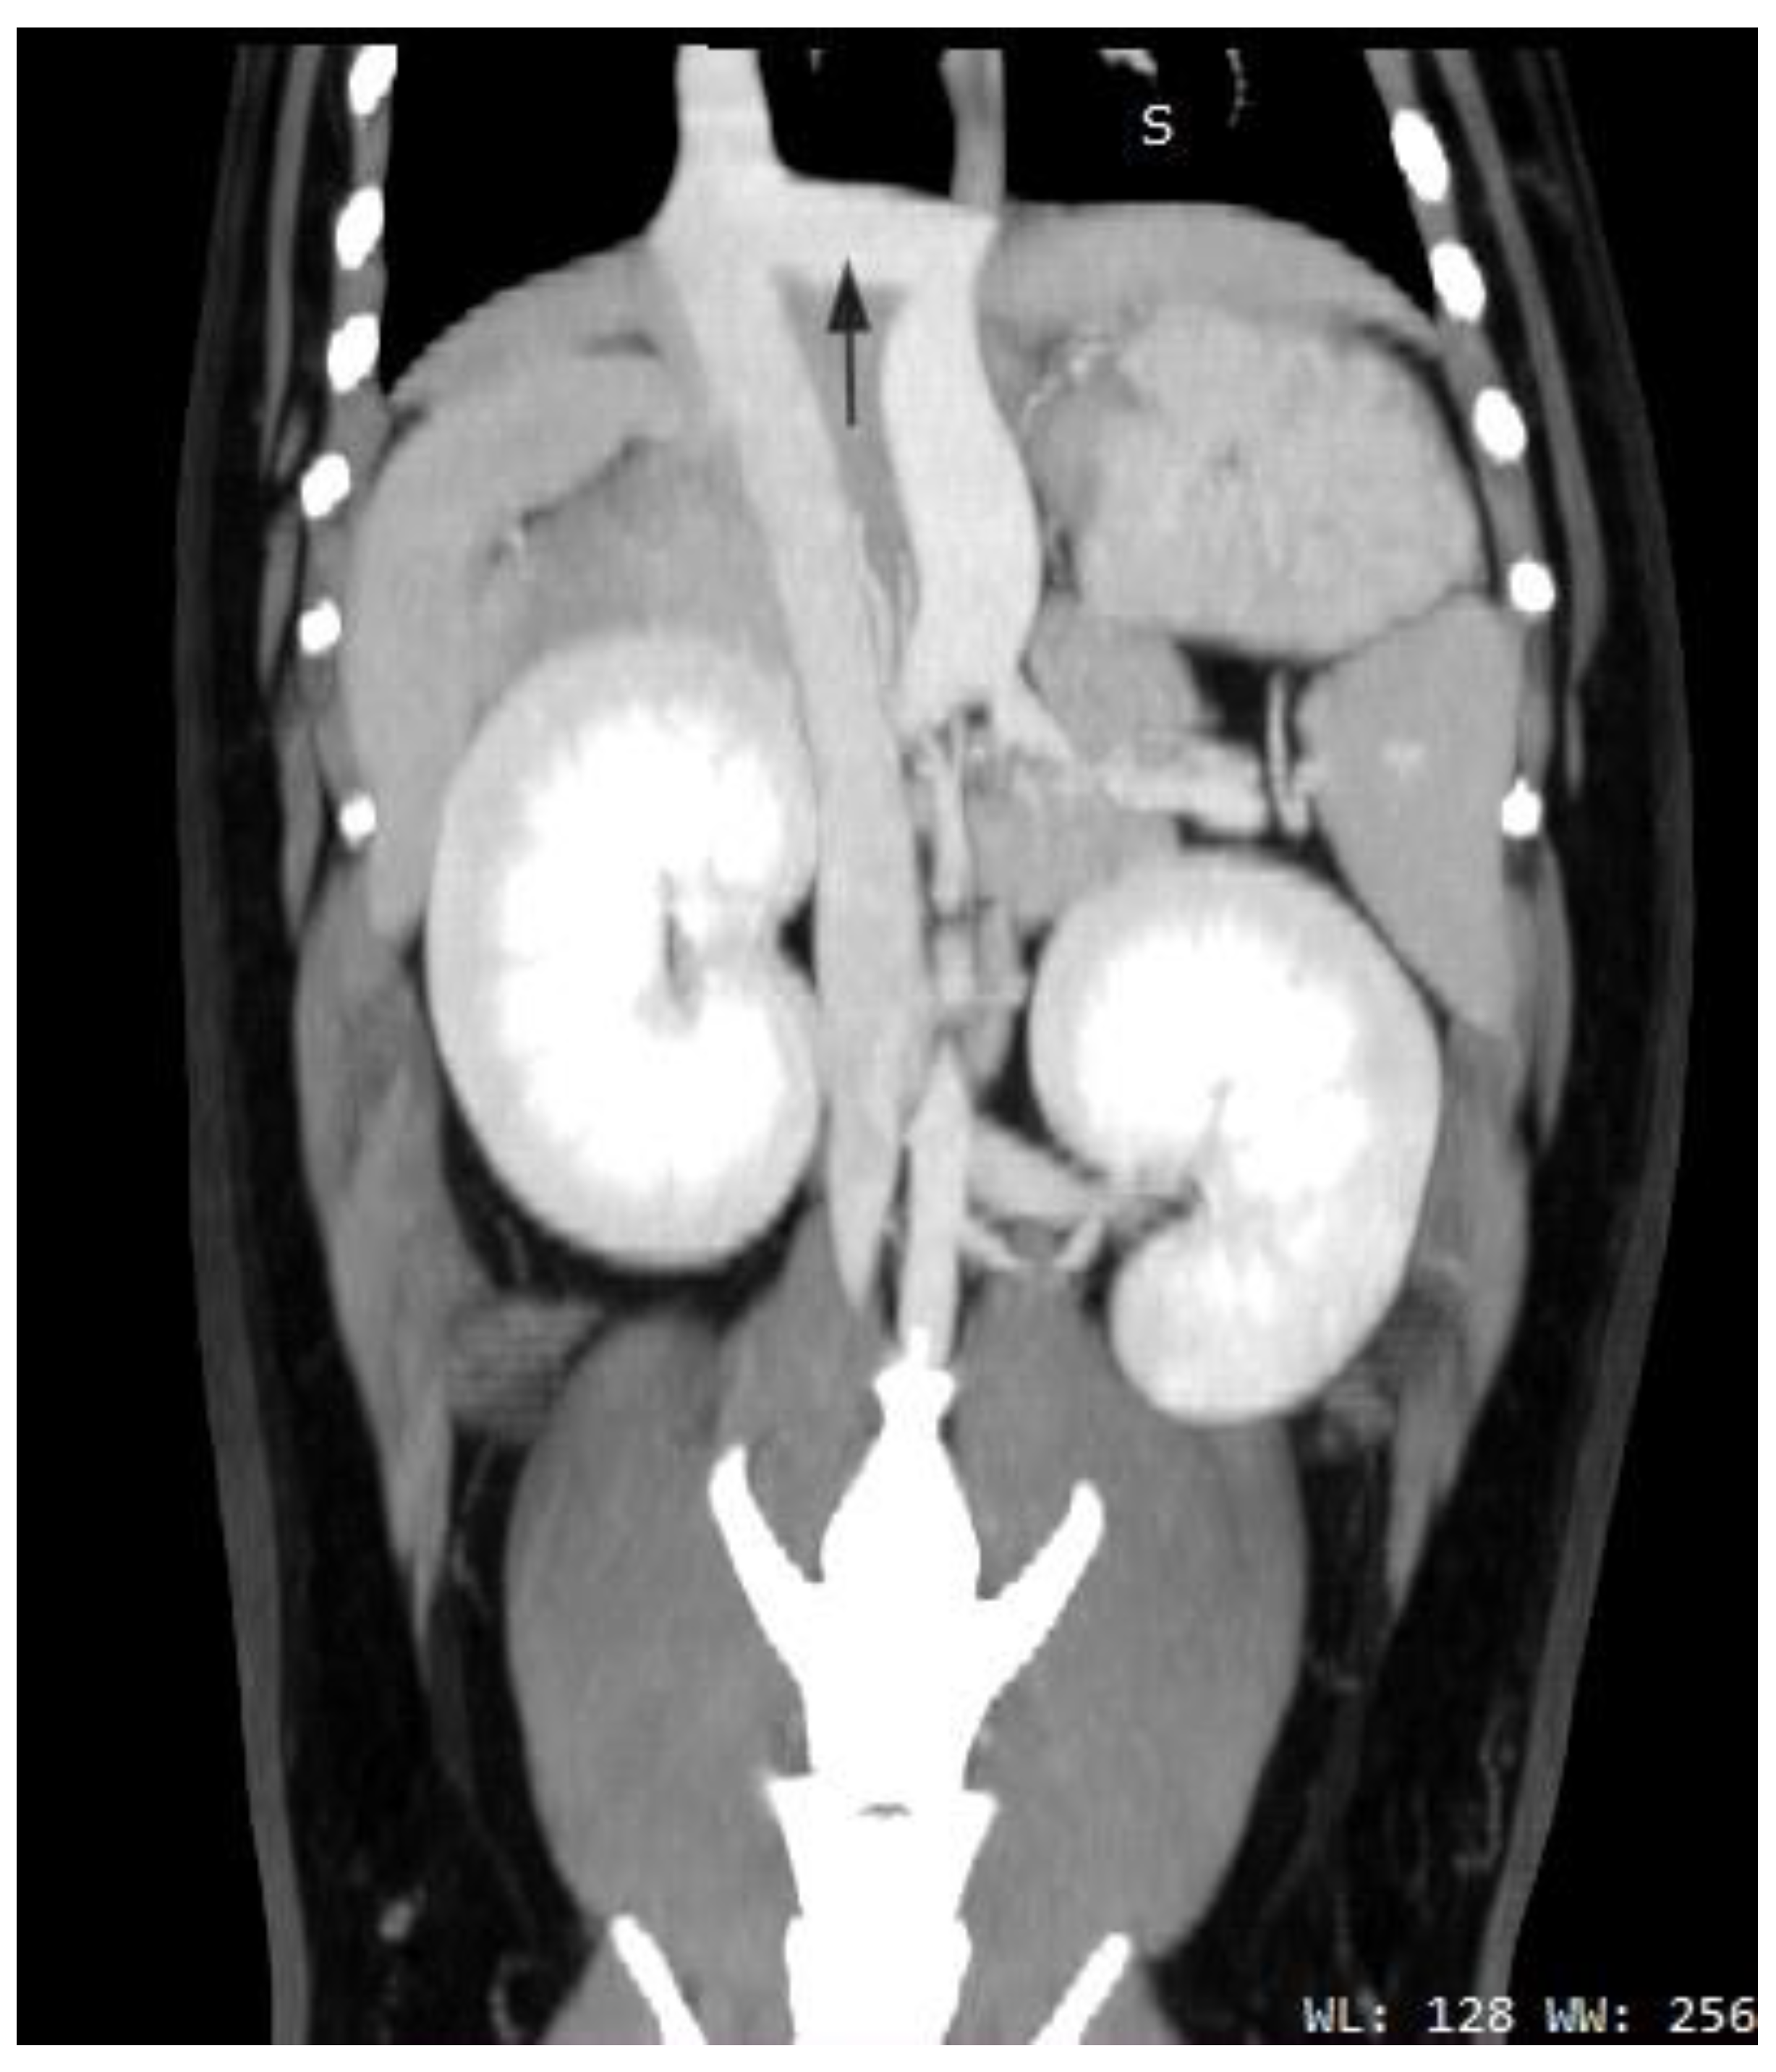

2.3. Case C (Dog)

2.4. Case D (Dog)